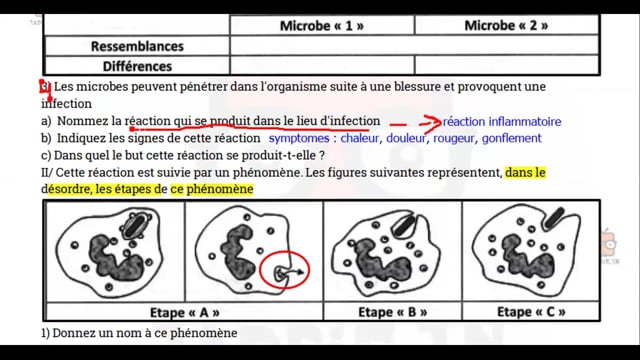

Sciences SVT

1ᴱ̀ᴿᴱ année